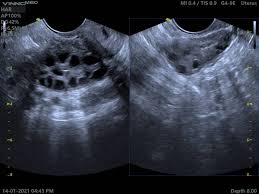

Pemeriksaan PCOS USG atau ultrasonografi ini sangat penting. Melalui USG, dokter bisa melihat kondisi rahim dan indung telur secara visual. Tujuan utama dari PCOS USG adalah untuk mendeteksi ciri-ciri fisik yang sering terlihat pada wanita dengan PCOS, seperti kista-kista kecil di ovarium yang menyerupai ‘untaian mutiara’. Memahami prosedur ini bisa membantu Anda merasa lebih siap dan tenang sebelum menjalani pemeriksaan.

Ketika Anda menjalani PCOS USG, dokter akan mencari beberapa karakteristik utama pada ovarium Anda. Ciri-ciri ini adalah kunci untuk menegakkan diagnosis. Karakteristik paling khas adalah adanya “kista” kecil di dalam ovarium. Namun, penting untuk dipahami bahwa ini bukanlah kista sungguhan dalam arti benjolan besar yang berbahaya.

Kista-kista ini sebenarnya adalah folikel-folikel kecil yang gagal berkembang dan matang. Folikel-folikel ini kemudian menumpuk di tepi ovarium, menciptakan gambaran khas yang sering disebut sebagai ‘untaian mutiara’ (string of pearls). Dokter akan menghitung jumlah folikel ini dan mengukur volume ovarium. Diagnosis PCOS USG bisa ditegakkan jika memenuhi kriteria tertentu, seperti adanya 12 atau lebih folikel di satu ovarium atau jika volume ovarium terlalu besar. Kombinasi dari gambaran ini, bersama dengan gejala klinis (seperti haid tidak teratur dan kadar hormon tinggi), sangat membantu dalam menentukan apakah Anda benar-benar memiliki PCOS.